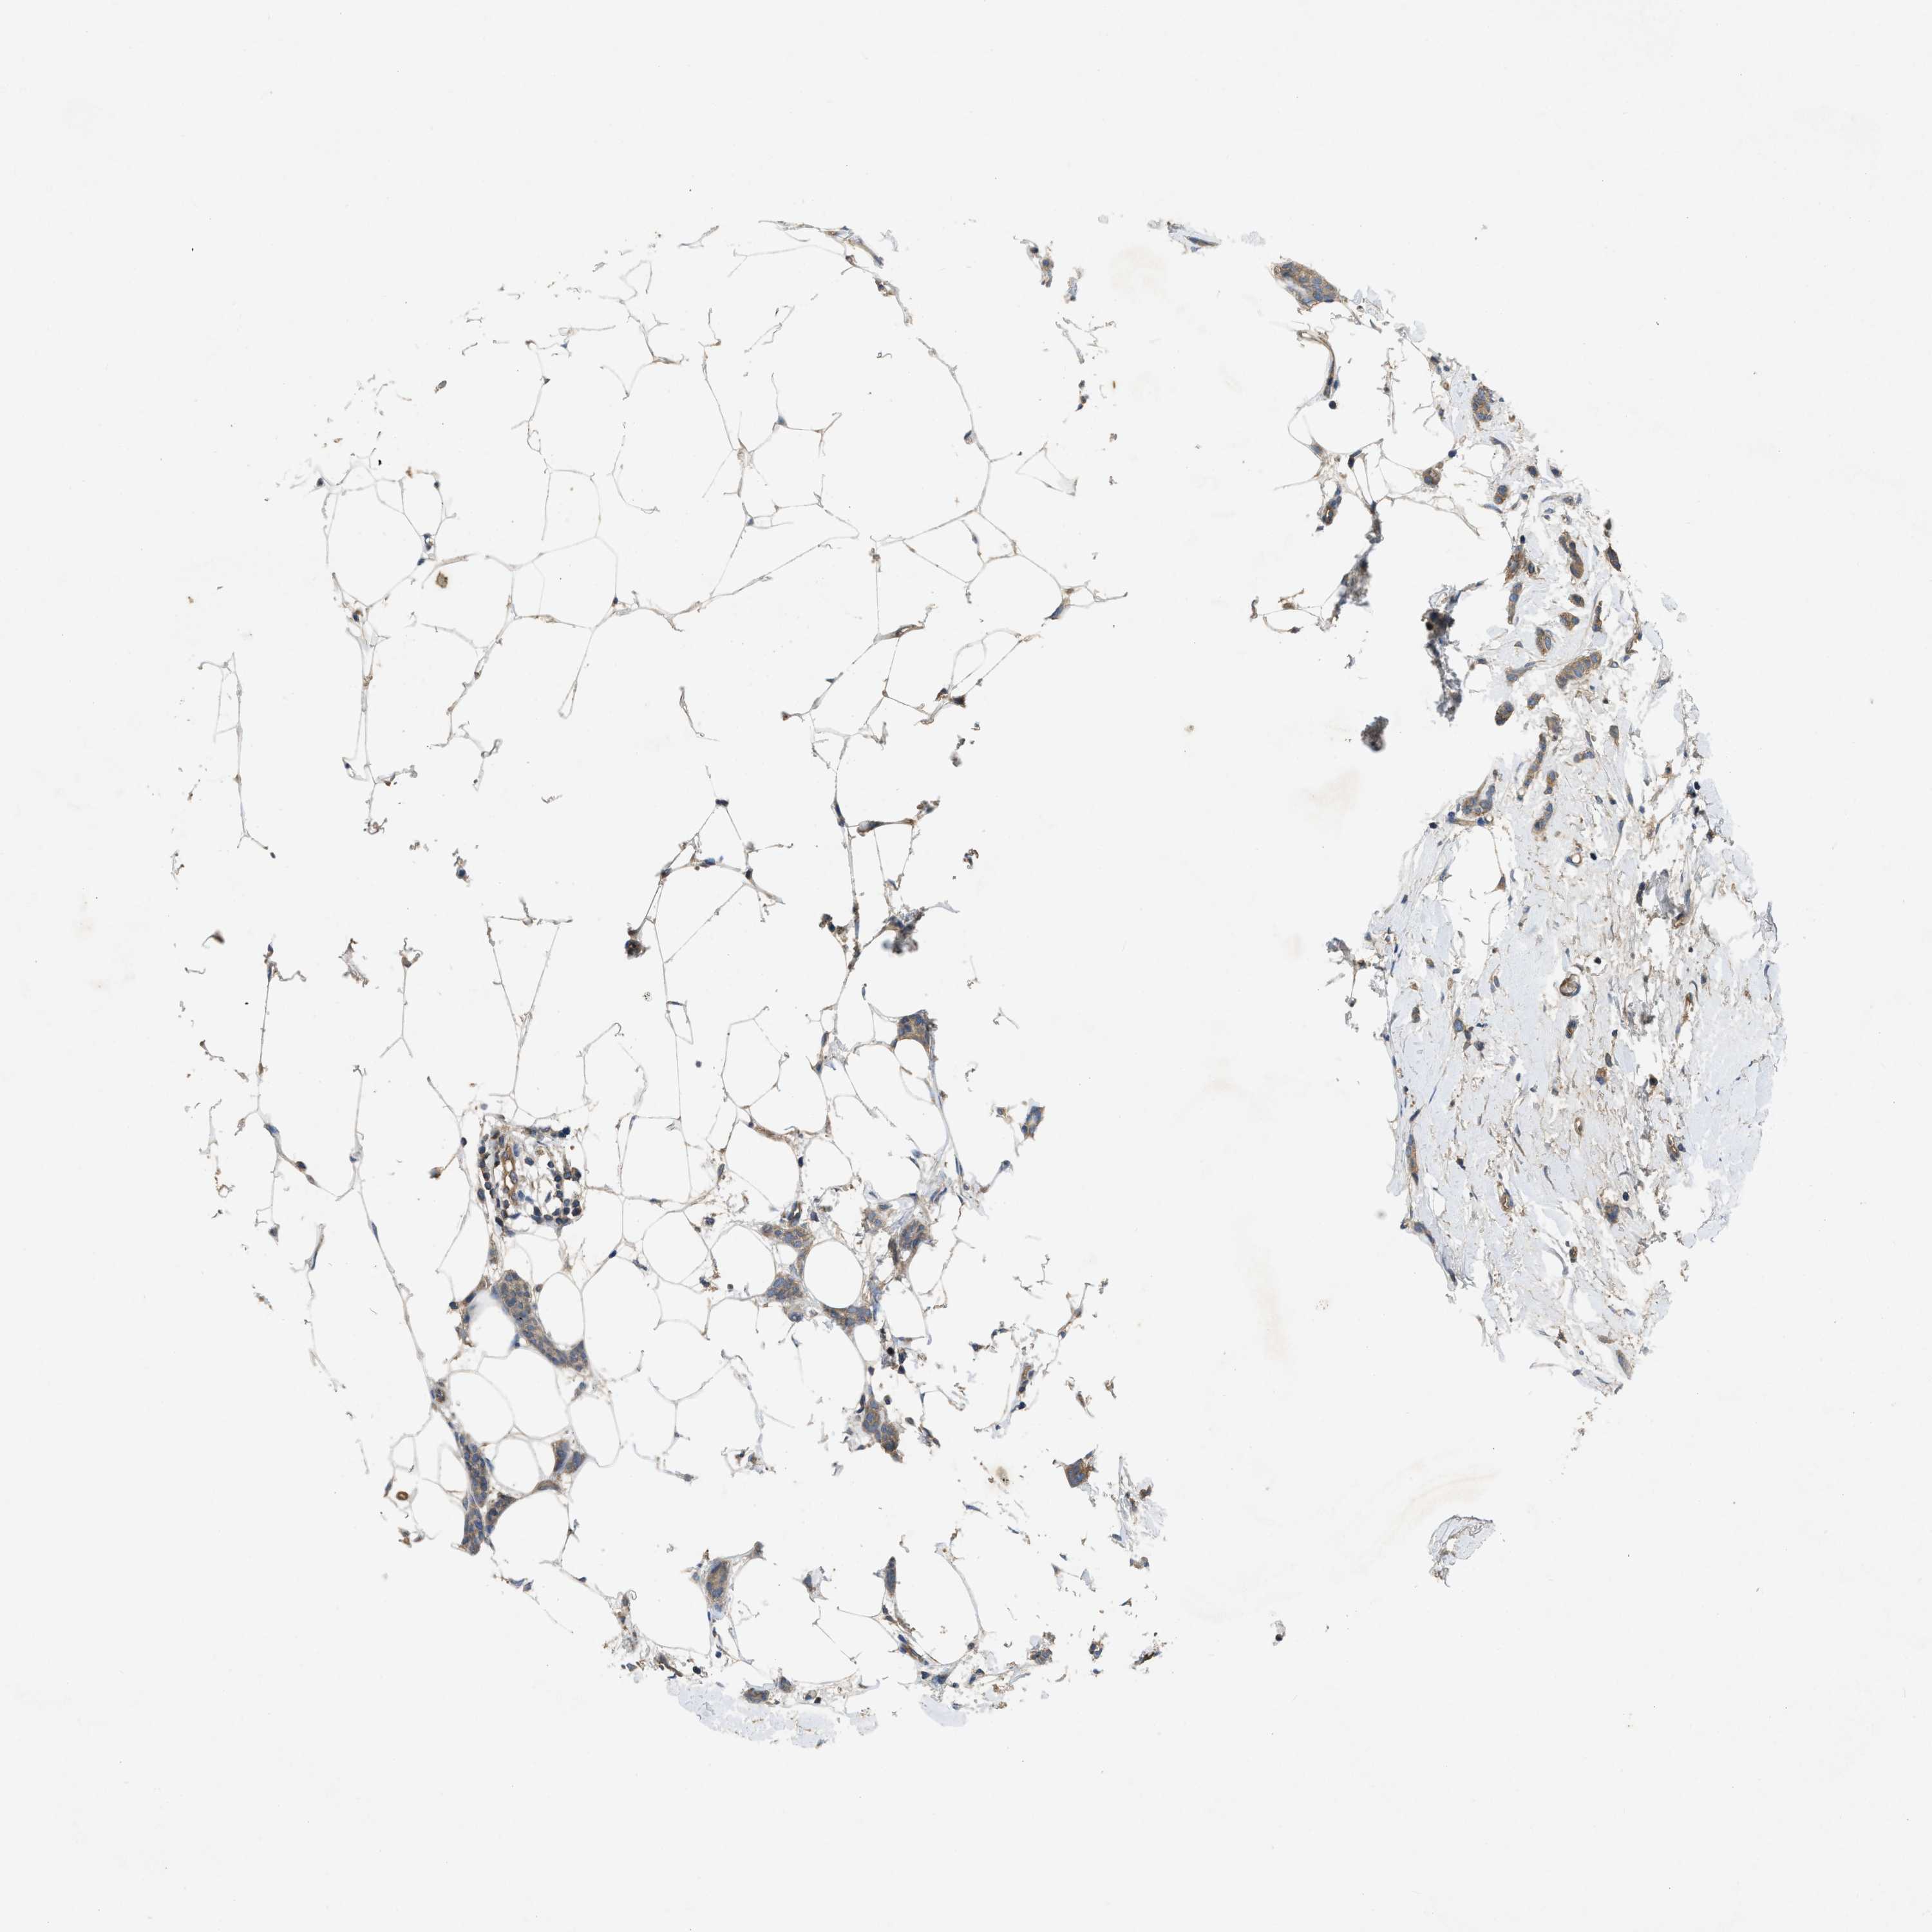

CANCER BREAST CANCER Show tissue menu

BRCA TCGA BRCA VALIDATION PROTEIN EXPRESSION